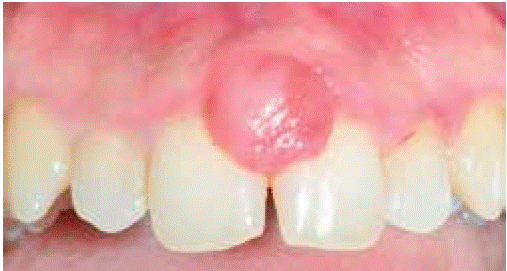

Clinical examination revealed an inflammatory gingival lesion at the site of teeth 1.1 and 2.1. The lesion measured 9x9 mm approximately and covered one third of the clinical crown; the lesion was asymptomatic, firm, lobulated, of rugged texture, bleeding upon stimulus (Figure 9). Periodontal evaluation did not reveal periodontal pockets, nevertheless, presence of plaque was observed; oral hygiene index of 50% (O'Leary) was obtained.

Radiographic examination revealed bone crest alteration between teeth 1.1 and 2.1 (Figure 10).

Presumptive diagnosis: pyogenic granuloma.

Treatment: fist session devoted to oral hygiene instruction followed by excisional biopsy of the lesion and gingivoplasty (Figures 11and12).